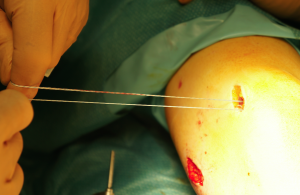

All’inizio bisogna misurare bene dove fissare il neo legamento

ecco fissato il punto giusto